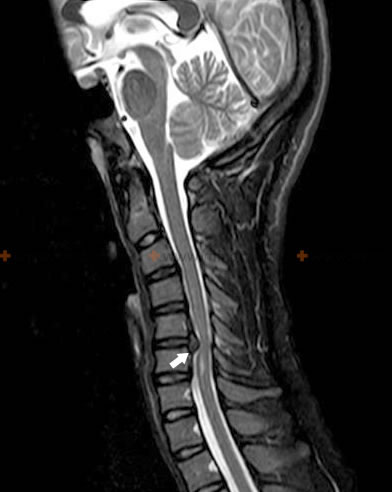

მაგნიტურ-რეზონანსულ ტომოგრაფიაზე აღმოჩენილია ატლას-აქსისის სახსრის არტროპათია და C2 მალის კბილისებრი წანაზარდის ეროზიული ცვლილებები, რომლებიც იწვევენ ზურგის ტვინის კომპრესიულ მიელოპათიას ხერხემლის რევმატოიდული ართრიტის მქონე პაციენტში.

ექიმები ხშირად ვერ ამჩნევენ რევმატოიდული ართრიტით გამოწვეულ გართულებებს, რომლებიც ზემოქმედებენ ზურგის ტვინზე. კისრის მალების სხეულების ან ატლანტის წინა ქვეამოვარდნილობას კისრის მეორე მალასთან (C2) მიმართებით შეუძლია გამოიწვიოს ზურგის ტვინის მნიშვნელოვანი დაზიანება, ლეტალური შედეგიც კი მცირე ტრავმის შემდეგ კომპრესიის შემთხვევაში (შოლტისებრი ტრავმა, კისერ-კეფის სინდრომი). უფრო მსუბუქ შემთხვევაში ავადმყოფს შეიძლება განუვითარდეს ქრონიკული კომპრესიული მიელოპათია, რომელიც ჰგავს ასეთივე მიელოპათიას კისრის სპონდილოზის დროს. C2 მალისაგან კბილის მოტეხას შეუძლია გამოიწვიოს ხერხემლის არხის ზედა ნაწილის შევიწროება (სტენოზი) ზურგისა და მოგრძო ტვინის შეერთების კომპრესიის თანხლებით, განსაკუთრებით კისრის მოხრის მდგომარეობაში თავის წინ დახრისას.